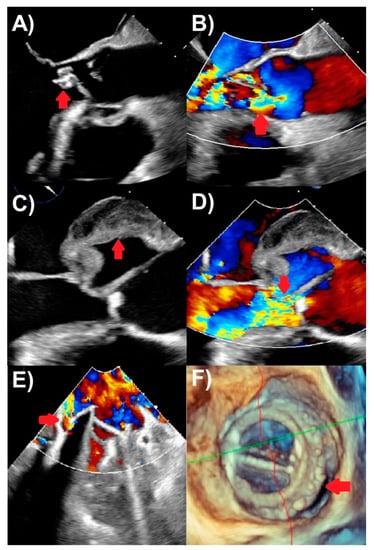

TEE is recommended for the vast majority of IE patients in absence of contraindications, because of its superior sensitivity and specificity to TTE from high spatial and comparable high temporal resolutions [20,21]. TEE is the best modality for evaluating vegetations, valve perforation, and prosthetic valve dehiscence, also performing well to identify pseudoaneurysm, abscesses, and fistulas (Figure 1). A comprehensive TEE examination should also be performed when assessing for IE, focusing on all four heart valves in esophageal and transgastric views [19]. In particular, contemporary three-dimensional echocardiography, including multi-planar reconstruction, is critical for the accurate depiction of the presence of IE, for its etiology and features, and usually more accurate for TEE than TTE. Clinical scenarios to use TEE include when TTE is inconclusive for IE, but there is a moderate-to-high clinical suspicion for IE; TTE is negative, but there is ongoing high clinical suspicion for IE; and TTE showing features of IE, but further evaluation for complications (such as new heart murmur, high-grade heart block, suspected abscess, embolic events, and heart failure) is required [1,2]. The last of these indications makes an argument for routinely performing TEE in all patients with IE, as TTE may miss important IE complications. TEE also plays an important role in assessing patients with prosthetic valves or intracardiac devices where TTE is less accurate and more prone to artifacts. TEE is not usually required if IE suspicion is low and TTE is negative [2]. Finally, intraoperative TEE is used for patients undergoing IE surgery to assess the extent of IE complications and the surgery needed, as well as for assessing the surgical result [1]. TTE and TEE are the cornerstones of first-line imaging modalities to assess endocarditis in all IE guidelines [1,2,22].

Figure 1. Transesophageal echocardiography findings of endocarditis. (A) Aortic valve vegetation (arrow), with (B) severe aortic regurgitation (arrow) on color Doppler. (C) Aortic with echolucent space consistent with pseudoaneurysm and abscess (arrow), with (D) severe aortic regurgitation (arrow) on color Doppler. (E) Mechanical mitral valve replacement paravalvular regurgitation (arrow) associated with (F) prosthetic valve dehiscence (arrow) seen on three-dimensional assessment.